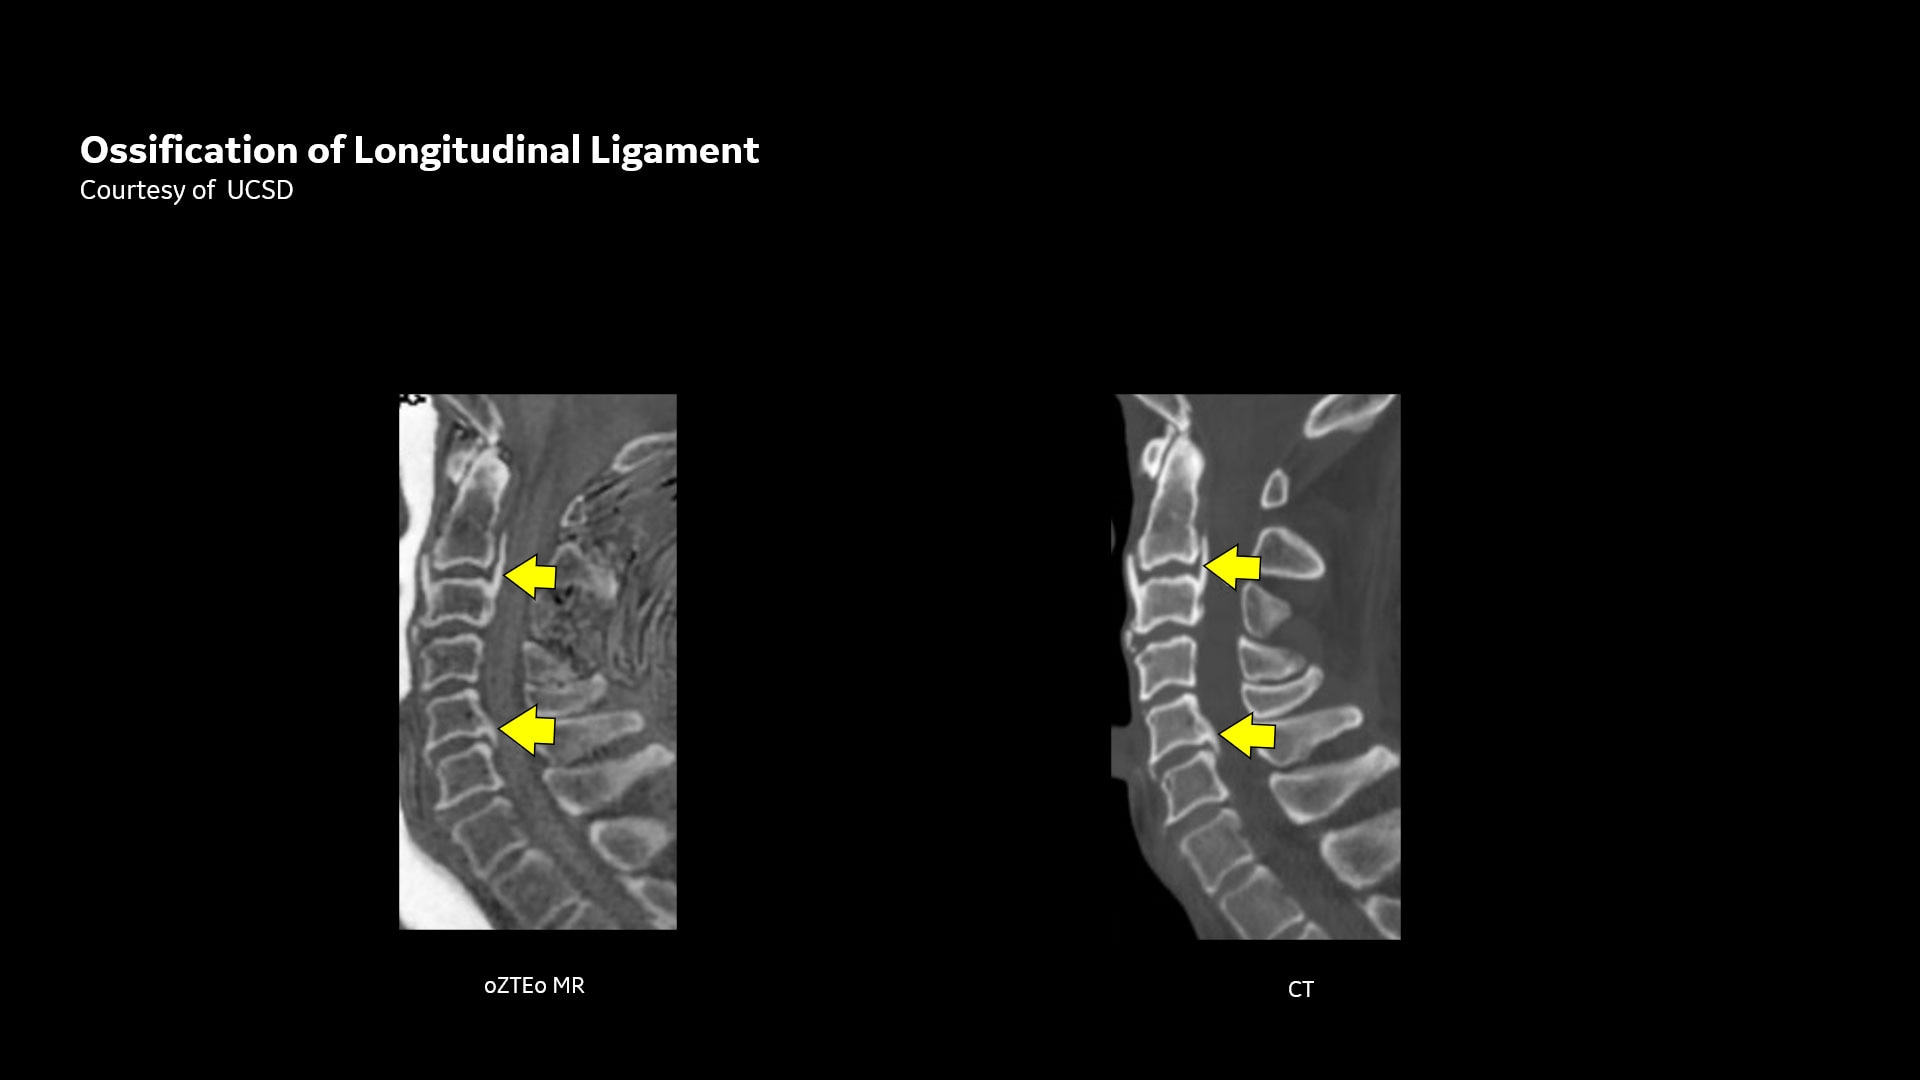

Mit dieser neuen Anwendung zur Darstellung von kortikalen Knochenoberflächen, basierend auf der radialen ZTE-Anwendung, können Sie eine neue Möglichkeit für die Knochenbildgebung anbieten und einen erheblichen klinischen Nutzen für Ihre orthopädischen Untersuchungen gewinnen.

oZTEo ist für alle Anatomien ohne ionisierende Strahlung verfügbar und liefert dabei Bilder von Knochenmorphologie, Verkalkungen, Verknöcherungen und Frakturen. OZTEo ergänzt die herkömmliche MRT-Weichteilgewebeuntersuchung mit perfekter Anpassung und bietet isotropische 3D-Bildgebung unter Verwendung einer radialen ZTE-Erfassung (Zero TE) mit inhärenter Unempfindlichkeit bei Bewegungen. Verwendung von oZTEo mit Volumenbeleuchtung für realistisches 3D-Rendering.

CT-ähnlicher Bildkontrast ohne ionisierende Strahlung

Die MRT-Knochenbildgebung liefert einen CT-ähnlichen Bildkontrast ohne ionisierende Strahlung und ist daher eine ideale Alternative für pädiatrische Patienten und Schwangere, für die ionisierende Strahlung problematisch ist. Darüber hinaus stellt dies eine willkommene Alternative dar, wenn CTs im Verlauf erforderlich sind, insbesondere wenn Niedrigdosis-CT-Systeme nicht verfügbar sind.